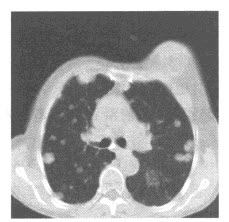

女,19岁,低热,盗汗,乏力,咳嗽1月余,CT检查如图,最可能的诊断是()

A.间质性肺炎

B.弥漫型肺癌

C.粟粒型肺结核

D.矽肺

E.大叶性肺炎